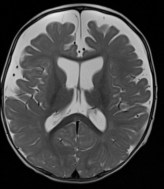

- l’échographie montre que le liquide est situé dans l’espace sous-arachnoïdien et non sous-dural, sachant que les deux peuvent co-exister. la valeur limite de la distance sinus sagittal- cortex est classiquement de 6 mm. les ventricules sont souvent légèrement dilatés également.

-

l’IRM identifie les veines et distingue l’épanchement sous-arachnoïdien du sous-dural qui lui est parfois associé. elle permet aussi de distinguer les macrocranies essentielles vraies des autres causes de macrocrânie : macrocéphalie vraie (syndrome de Sotos)